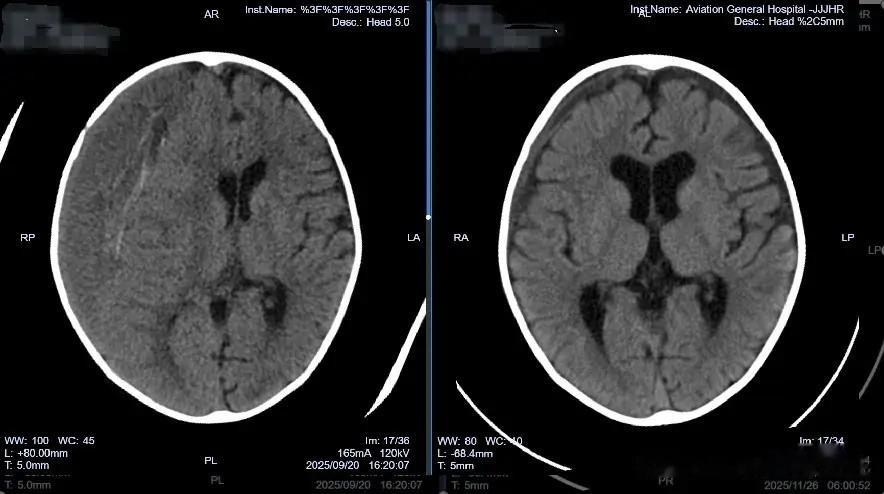

随后的日子里,这个年幼的孩子经历了双侧硬膜下引流、Ommaya囊植入定期穿刺、因金黄色葡萄球菌感染而进行的脑室外引流......一次次治疗,一次次复发,又一次次加重,左侧硬膜下积液还未完全好转,右侧硬膜下积液内部又出现分隔样改变,这种分隔意味着积液被分割在多个互不相通的“小房间”里,常规穿刺引流难以全面清除,病魔如同建立起顽固的壁垒,让传统治疗方法束手无策。

通过放置在腹壁外的引流管,医疗团队每天监测引流情况,并逐步调整引流瓶高度,促进大脑自然复位。这一外引流设计避免了在感染风险期植入永久性分流装置。经过近两个月的恢复,2025年11月底,瑶瑶再次接受手术,移除了硬膜下-腹腔分流管。次日复查头颅CT显示:双侧硬膜下仅残留少量低密度影,脑组织复位良好,中线结构居中。